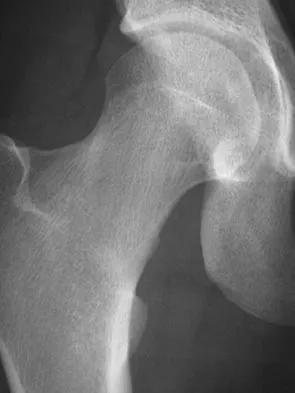

Figure 36 shows the radiograph of a patient who has hip pain and is unable to ambulate. What is the most appropriate management for this patient?

Explanation

The patient has a periprosthetic fracture of the greater trochanter - Vancouver A. The reason for the fracture of the greater trochanter is the extensive periarticular osteolysis that has occurred as a result of polyethylene wear. The latter is demonstrated by eccentric seating of the large femoral head in the acetabulum. The most appropriate management is to reverse the osteolysis process, which involves exchange of the acetabular liner with or without revision of the other components depending on their fixation and position. The greater trochanter can also be fixed during revision surgery. Duncan CP, Masri BA: Fractures of the femur after hip replacement. Instr Course Lect 1995;44:293-304.